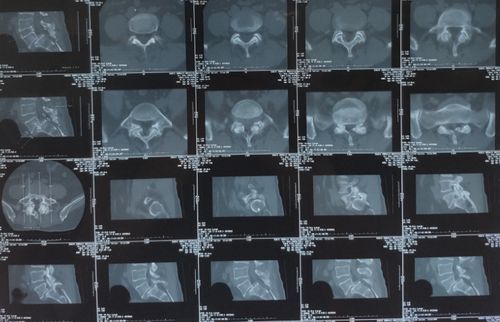

椎弓峡部裂ct诊断图片

椎弓峡部裂ct诊断图片,椎弓峡部裂解剖

【s077】椎弓峡部裂

早期椎弓峡部裂.男,10多岁.

期刊反角度ct扫描诊断腰椎椎弓峡部裂的临床价值 目的探讨反角度

医影基础 | 图文详解椎弓峡部裂

诊断:腰5椎体滑脱症(3度);腰5双侧椎弓峡部裂. vas评分:6分.